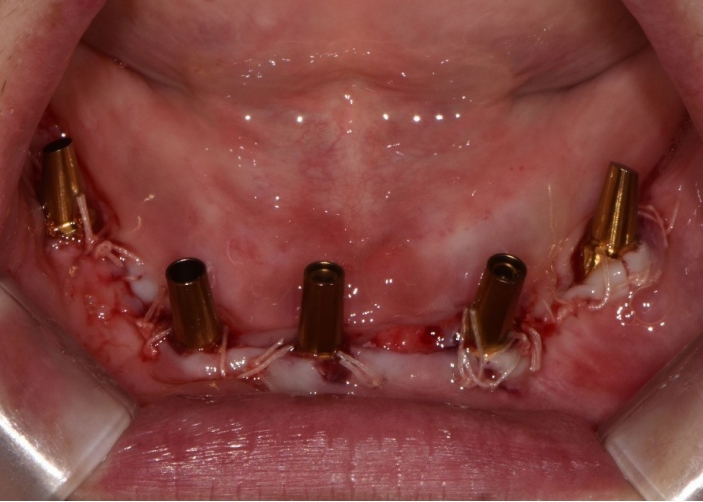

수술 당일 이중 가이드를 구내에 장착하여 하부가이드를 고정 핀으로 고정시킨 후(Fig. 9), 계획된 위치에 임플란트 고정체를 식립하였다. 임플란트는 5개 모두 외부 연결형 고정체(AnyOne External, Megagen, Seoul, Korea)를 사용하였고, 식립 시 식립 토크는 모두 40N 이상, ISQ는 70이상으로 양호한 초기 고정력을 확보하였다(Fig. 10). 즉시 부하를 위해 기성 어버트먼트를 체결하였고, 임시 보철물을 장착하여 양측 소구치부에서의 균일한 교합을 확인하였다(Fig. 11).

Fig. 9.

Surgical guide is fixed on residual alveolar ridge.

Fig. 10.

Angled temporary abutment is connected to the surgically placed implant fixture.